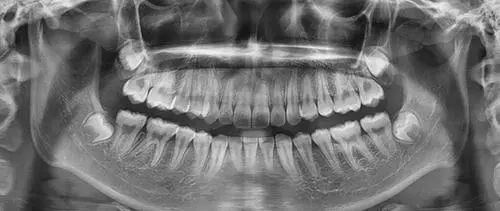

When the root tube is treated, it is necessary to take a tooth and at least three are guaranteed。

(b) the first, prior to treatment, helps doctors to understand the basics of the tooth root and develop treatment plans

The second, in treatment, helps doctors to understand the treatment, e. G., whether the root tube is in place, etc., and to develop the next course of treatment

The third is to help determine the quality of the root tube fillings after the end of treatment and to detect problems and remedy them in a timely manner。